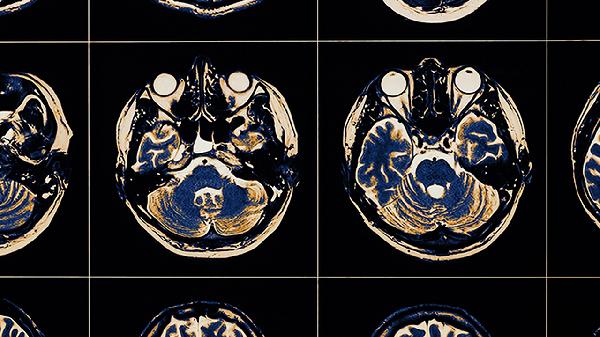

腦血栓中風(fēng)后遺癥怎么治療

腦血栓中風(fēng)后遺癥可通過康復(fù)訓(xùn)練、藥物治療、物理治療、心理干預(yù)、手術(shù)治療等方式改善。腦血栓中風(fēng)后遺癥通常由腦組織缺血缺氧導(dǎo)致神經(jīng)功能損傷引起,表現(xiàn)為肢體癱瘓、語(yǔ)言障礙、吞咽困難等癥狀。